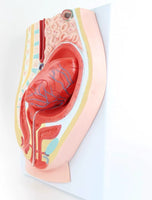

Modelo de desprendimiento separacion de placenta

Este modelo es una sección sagital del abdomen y la cavidad pélvica femenina con volumen uterino y superficie de inserción pélvica reducidos después del parto, que muestra la estructura morfológica del útero, la vagina, la placenta y el cordón umbilical.

Las superficies fetal y materna de la placenta tienen una forma realista, la parte inferior del útero está ligeramente hacia arriba y continúa contrayéndose, cerca del bulto abdominal inferior de la sínfisis del pubis y el cordón umbilical que cuelga en los genitales (signos de desprendimiento de placenta). ).

se desprende la parte central de la placenta y se baja al segmento inferior de la cavidad uterina.